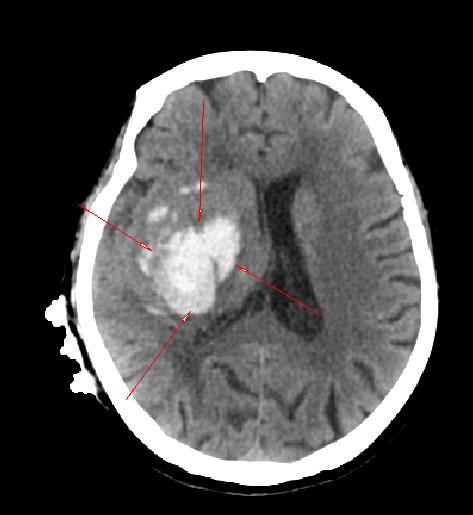

术前CT

患者张阿姨患有高血压、冠心病,并有脑梗病史,长期接受抗凝治疗。发病当日,她午饭后突感头晕、左腿无力并摔倒,伴随呕吐,随即意识不清、无法言语,被紧急送至我院急诊。经检查,确诊为“右侧基底节区脑出血”。该部位出血常致偏瘫、昏迷,风险极高,加之患者年事已高、长期服用抗凝药物,更使治疗面临严峻挑战。